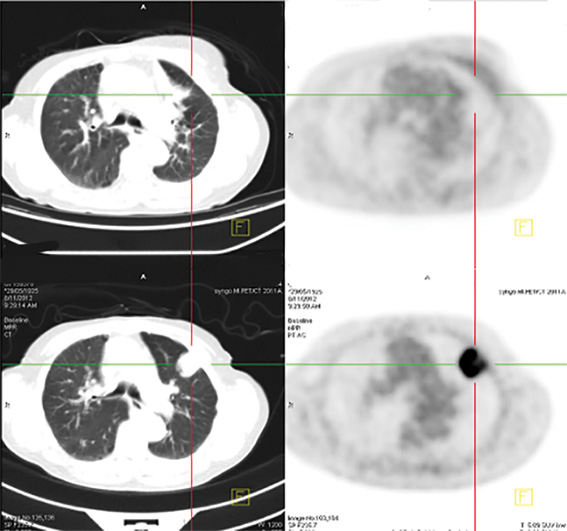

Stereotactic radiation treatment uses advanced imaging technology to deliver a high dose of radiation, very accurately and precisely to a tumour, sparing the surrounding sensitive organ.

“Stereotactic provides six times the strength of a conventional radiation dose, and is suitable for treating tumours less than five centimetre in diameter—generally early-stage cancers.